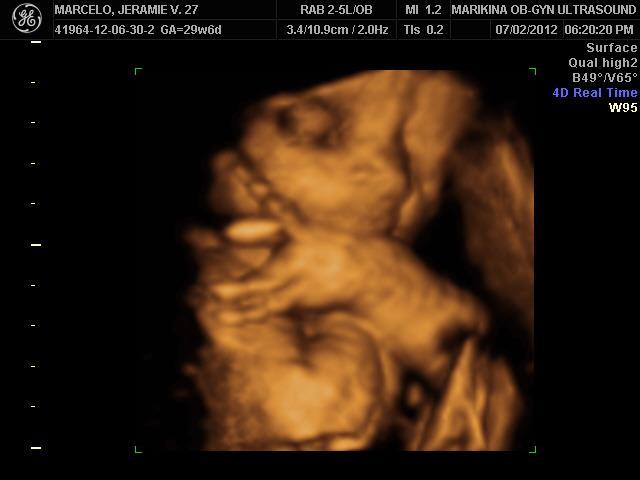

3d 4d Ultrasound In Marikina

Third Trimester Changes Tests And Preparations For The Big Day Happy Mommy Adventures